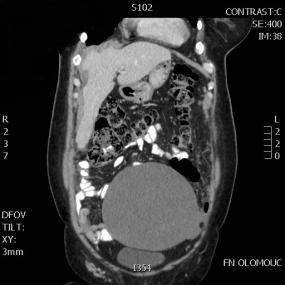

Ukázka obrazové dokumentace:

1. objemný tumor dutiny břišní s karcinomatózou peritonea před léčbou

2. kontrolní CT sken stejné nemocné po kompletní cytoredukci a HIPEC